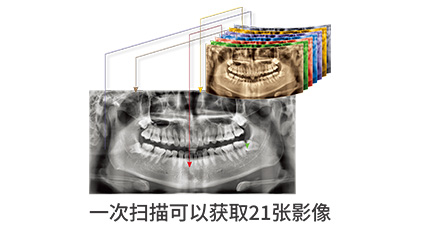

一次扫描获取21张影像,将每张清晰的区域自动重建为一张高清影像,大大节省了重新拍摄以及和患者沟通的时间。同时可清楚拍摄前牙区、根尖区、上颌窦底、TMJ等部位的口腔影像。

Green 16搭载PA集团官网自主研发TGG-ai绿能技术,这项技术可有效缩短曝光时间,同时在16X15的视野下可自动融合高品质影像。